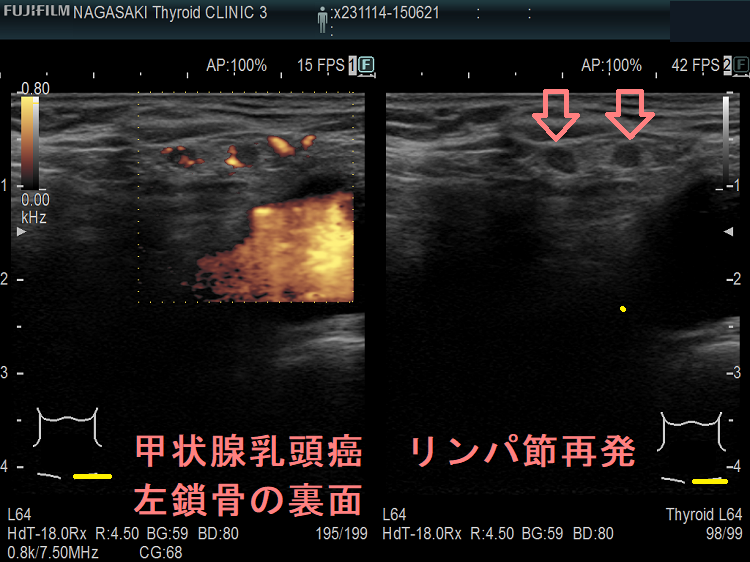

甲状腺乳頭癌鎖骨の裏 リンパ節転移再発

甲状腺乳頭癌 リンパ節再発 左鎖骨の裏面

甲状腺乳頭癌 リンパ節再発 左鎖骨の裏面(拡大)